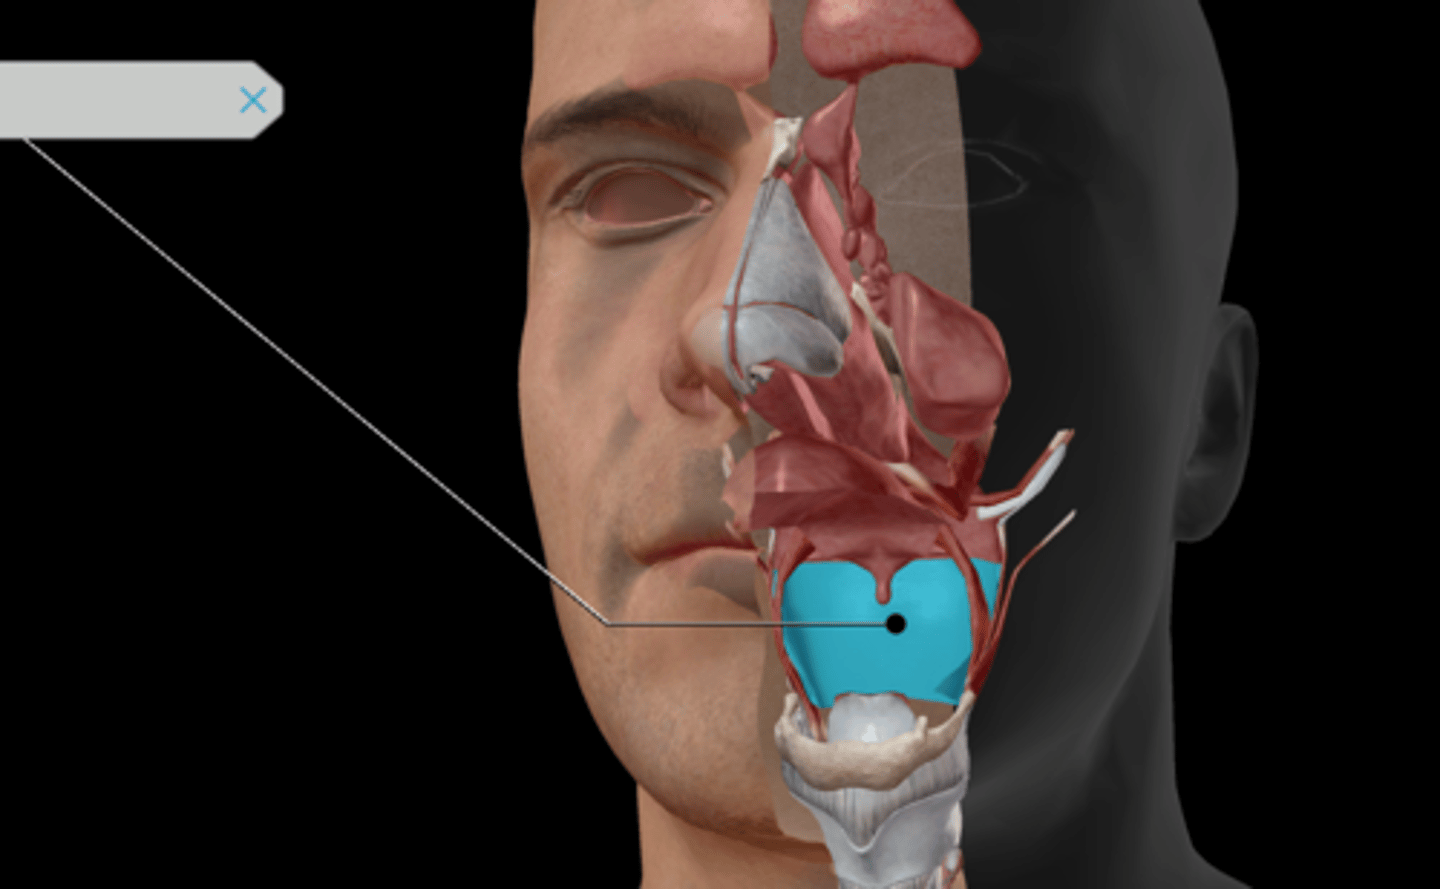

Nasal cavity

Nasal conchae

Nasal cartilages

Nasopharynx

Oropharynx